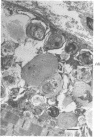

Patients with inclusion body myositis demonstrate characteristic histological and electronmicroscopical abnormalities in muscle and are generally considered refractory to treatment. A patient with inclusion body myositis is described with evidence of associated autoimmune disease, who responded to steroids.

Images in this article